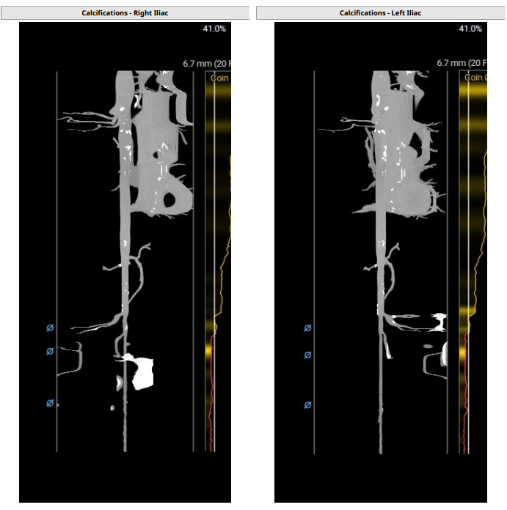

外周入路血管条件,主动脉弓、降主动脉及腹主动脉部分部位存在钙化。

双侧股动脉血管走形稍迂曲,未见明显钙化,双侧均为低分叉;髂总动脉—降主动脉走形平直,未见明显钙化;主动脉弓部走行相对顺滑。